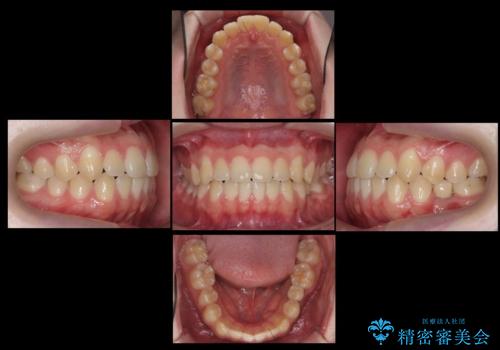

生まれつき歯が少ない 20代でインプラント治療

- 20代男性

- ワイヤー矯正

- 1年

- 左下の奥歯が生まれつき歯が少ない患者様です。

健康な歯を削らずに歯を入れたいとのことでした。

歯がなかった時期に隣の歯が移動してすき間があったため、部分的な矯正治療を行い、インプラントを入れるすき間を確保しています。